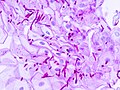

Microscopic

Features:

- Worm-like micro-organisms - key feature.

- Pseudohyphae (single cells).

- Thickness ~ 1/3-1/2 of squamous cell nucleus.

- Should be within (squamous) epithelium.

- Superficial inflammation - esp. neutrophils - important.

Notes:

- On top of epithelium does not count,[4] i.e. it is likely an artifact.

- Bacilli and cocci may accompany the candida. They are typically ignored.

Image